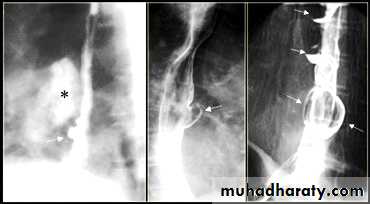

On the far left a traction diverticulum (arrow) due to hilar granulomatous disease. Calcified adenopathy (asterisk).

In the middle a pulsion diverticulum (arrow) due to high intra luminal pressure.

On the right multiple pulsion diverticula (arrows)